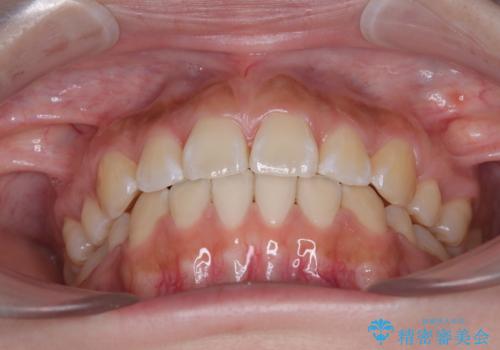

- 口元から飛び出てしまう前歯を気にして来院された患者様です。

上下前歯が嘴のように前方に突出しており、唇が閉じにくい状態であったため、上下左右の第一小臼歯4本を抜歯して、口元の突出感を改善することとしました。

目立たない装置を希望とのことで、上顎が裏側、下顎が表側のハーフリンガル装置を用いることとしました。